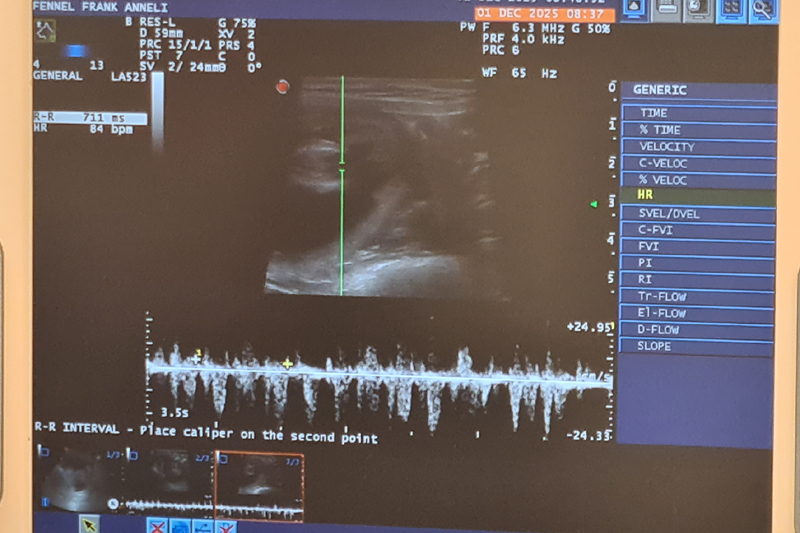

Två lyckade inseminationer!

Nu har vi varit med Fennel hos veterinären och gjort två inseminationer, en igår och en idag, och allt känns bra.

Hon är inseminerad med den engelska hanen Foxpath´s Comus som kallas för Remus. Nu håller vi tummarna!!